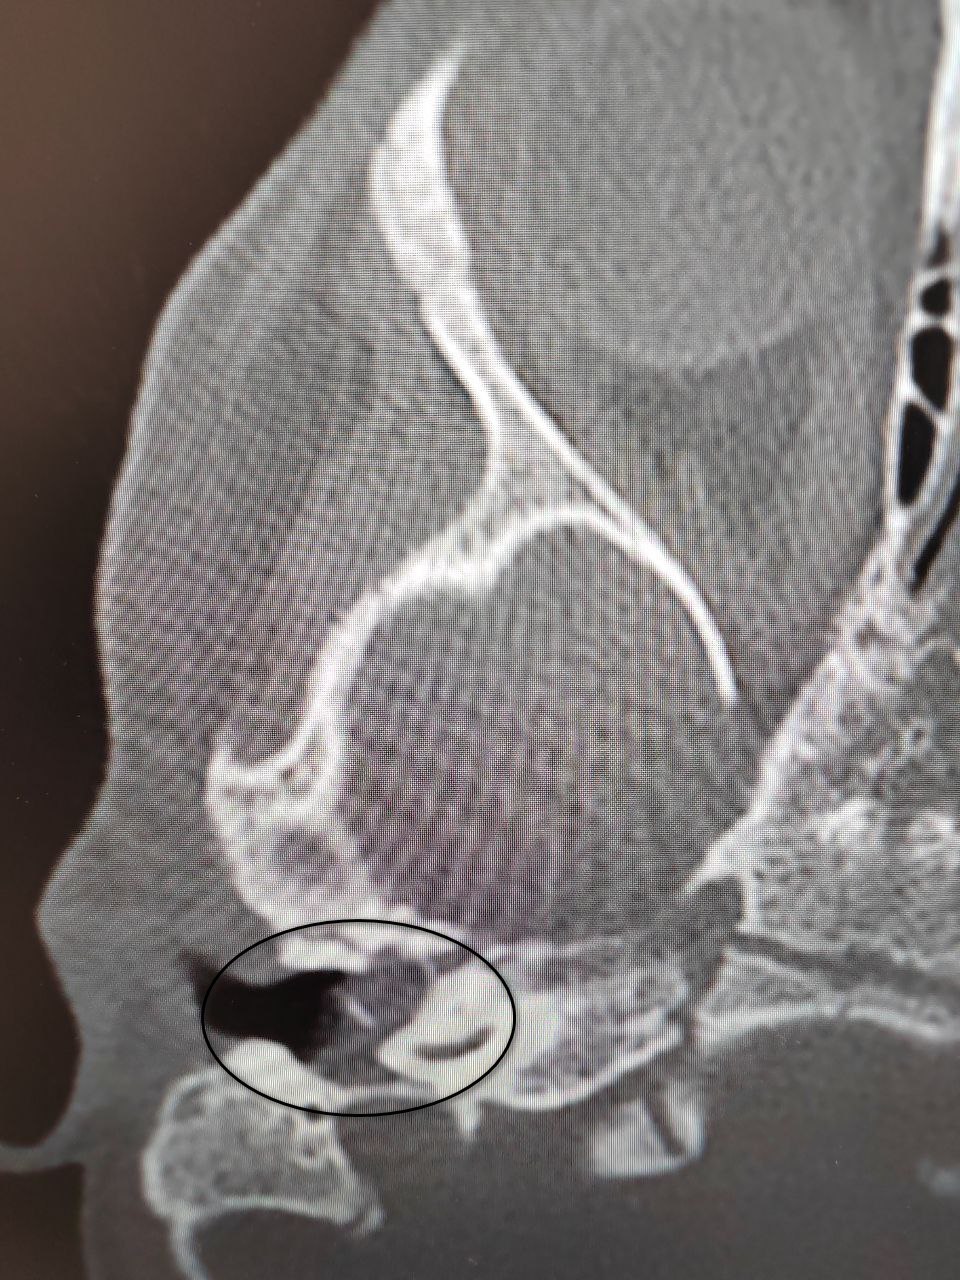

У ребенка был правосторонний хронический гнойный средний отит и подозрение на врожденную холестеатому барабанной полости (кистозное патологическое образование в среднем ухе). Это заболевание встречается особенно редко в таком раннем возрасте. Из-за холестеатомы девочка могла потерять слух.

После ОРВИ у ребенка появилась боль в ухе. Консервативное лечение не принесло результатов, ситуация осложнилась парезом лицевого нерва – слабостью мимических мышц. Врачи приняли решение о хирургическом лечении. Они удалили холестеатому и восстановили механизм звукопроведения.